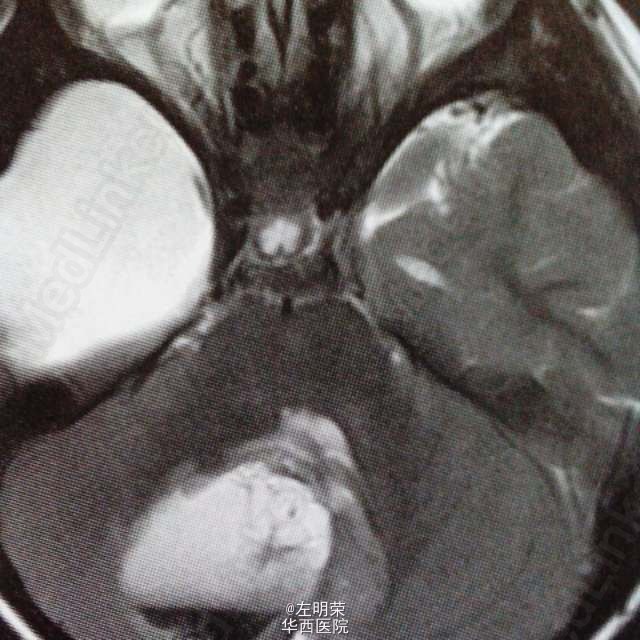

6岁小儿,主诉间断性头痛伴恶心,呕吐6天。影像特点:右侧小脑半球可见明显强化的囊实性占位,囊内可见出血后形成的液平,瘤旁轻微水肿。考虑星形细胞瘤,髓母细胞瘤,室管膜瘤可能。行手术切除治疗,见囊实性肿块,囊内坏死出血,肿瘤血供丰富,边界不清,近全切。病理结果:髓母细胞瘤